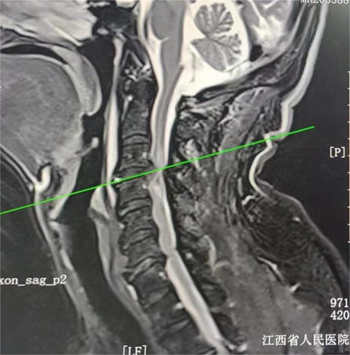

术前影像:患者颈3/4巨大椎间盘突出,脊髓受压变性

紧急接诊患者后,骨科行政主任陈钢教授团队第一时间为涂先生完善检查,发现患者既往就有颈椎病史,此次外伤后颈3/4椎间盘巨大突出,已经造成脊髓严重的变性损伤,患者四肢感觉运动完全丧失,呼吸越来越弱。据了解,颈椎损伤引起的高位截瘫在临床上恢复机会非常渺茫,因为神经很脆弱,一旦受到损伤,其所支配的四肢活动就难以恢复。这个时候,家属已经泣不成声,表示对患者恢复活动已不抱希望了,但是高位截瘫还会累及患者的呼吸肌,导致呼吸困难,病人的生命危在旦夕。龚飞鹏副主任医师耐心劝导患者和家属不要放弃,并立即着手准备急诊手术。